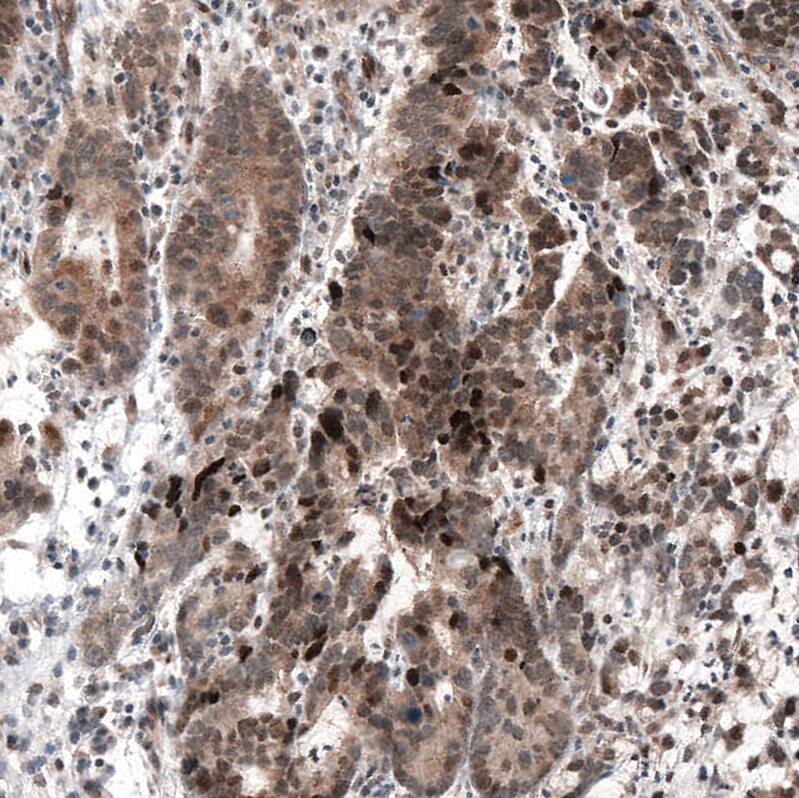

Staining of human stomach cancer shows moderate to strong cytoplasmic and nuclear positivity.